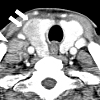

КТ щитовидной железы

МСКТ щитовидной железы. Это целенаправленное томографическое сканирование проекции железы, направленное на получение трехмерных и тонких трехмерных изображений органа. Имеет диагностическое значение при оценке размеров щитовидной железы и ее структуры, выявлении патологических процессов. Более того, это позволяет оценить состояние околощитовидных желез и лимфатических узлов шеи. МСКТ щитовидной железы помогает обнаруживать узелки, определять степень их распространенности и положения относительно соседних анатомических структур (трахеи, пищевода, яремных вен ). Для изучения регионарной гемодинамики процедуру проводят с внутривенным контрастным введением. Под контролем МСКТ, биопсия узлов щитовидной железы может быть проведена. сTMS щитовидной железы помогает определить показания и объем операции.